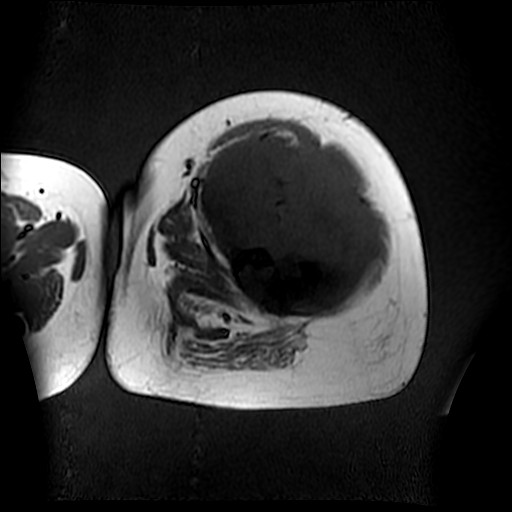

左侧大腿外伤10余年,当时情况不清,发现左侧大腿肿胀7年余,而后又有多次外伤史,近1年来出现疼痛,减重半年。查体:左侧大腿肿胀明显,皮温、肤色正常。

软组织肿块,股骨破坏,增强不均匀强化-----支持恶性肿瘤